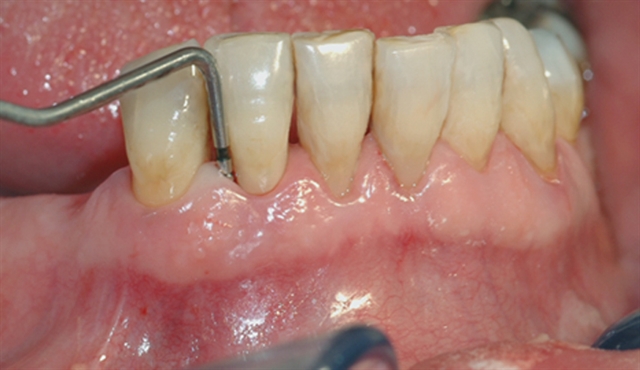

Instrumentet er her lagt utenfor tannkjøttet for å vise hvor stort festetapet egentlig er.